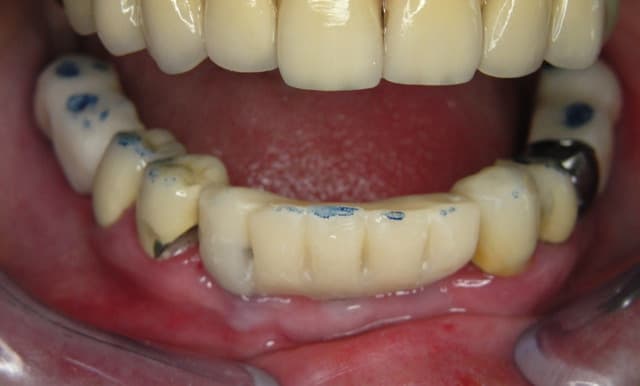

A défaut d'une chir en direct .. voilà une petite histoire en photos ou comment en 90 minutes passer d'un partiel résine à ...7 implants sur provisoires..stabilité primaire 60N grace à la technique MIMI ( oui.. post spécial ce Week end)..:)

Maintenant concernant la demande de scans : je poste ce cas, une patiente vient me voir avec son scan car elle a consulté d'autres "spécialistes" et on lui refuse la pose d'implant secteur 4 où alors avec greffe préalable..Ca se discute..pas de temps à perdre je sais faire autrement..

Avec la chir trans gingivale technique MIMI ( Oui..un post sur la technique bientôt ..) j'ai pu placer deux 3,5/8mm..aurai je eu le meme résultat avec un lambeau..j'en doute..Les couronnes sont en titane. Recul clinique 2 ans ras. Simple efficace rapide moins onéreux satisfaisant pour le praticien et la patiente..